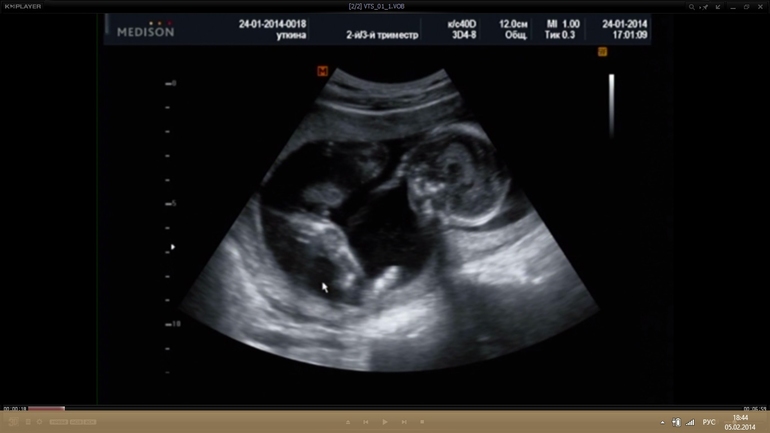

Первый скрининг не давал мне покоя и я решила провести самостоятельно внеплановое УЗИ в 16-17 недель..записалась в хорошую клинику в другом городе и ни разу не пожалела что туда попала, в дальнейшем все УЗИ делала только там. Можно сказать что тогда я первый раз увидела свою крошку, она танцевала у меня в животике, махала ручками и ножками, открывала ротик, в общем сколько эмоций я тогда пережила не передать словами, тогда мы узнали что ждем дочку, я ревела выйдя из кабинета от счастья..

Второй скрининг я уже делала в этом же центре в 20-21 нед, на котором у нас славу богу все было хорошо, девочку нам подтвердили, сказали примерный вес 362 гр.